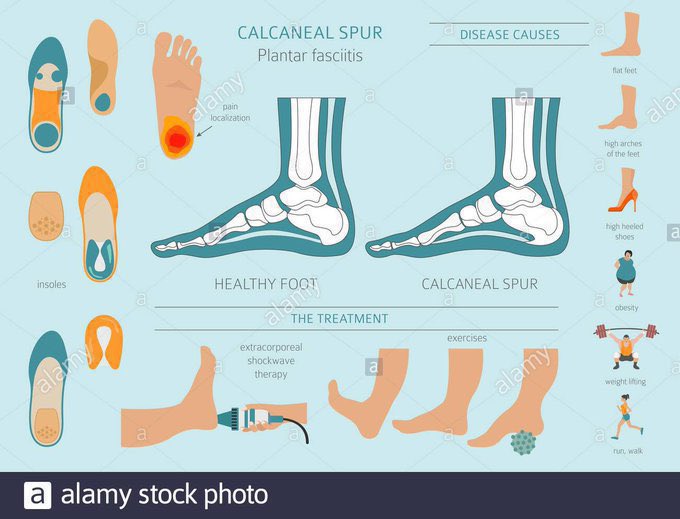

من هم عرضة للإصابة بالتهاب #اللفافة_الاخمصية ؟

♦️العمر: أكثر شيوعا بين عمر 40-60

♦️من لديهم ارتفاع او تفلطح في قوس القدم

♦️أنواع معينة من التمرينات التي تضغط ع الكعب

♦️ نمط المشي غير الطبيعي: الطريقة التي يتم بها توزيع الوزن عند الوقوف

♦️#السمنة

♦️نمط الحياة

الوقوف الطويل

♦️العمر: أكثر شيوعا بين عمر 40-60

♦️من لديهم ارتفاع او تفلطح في قوس القدم

♦️أنواع معينة من التمرينات التي تضغط ع الكعب

♦️ نمط المشي غير الطبيعي: الطريقة التي يتم بها توزيع الوزن عند الوقوف

♦️#السمنة

♦️نمط الحياة

الوقوف الطويل